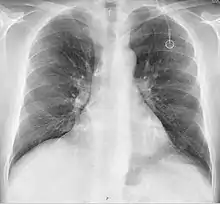

A follow-up on a chest radiograph can immediately detect complications associated with the procedure such as pneumothorax, hemothorax and malpositions of the catheter. However, routine chest radiography is not needed due to the low complication rates associated with the procedure. The chest radiograph is only done if there is clinical suspicion of a complication.[4]

The incidence of catheter fracture is 2.3%. The fracture can be due to "pinch-off syndrome" when the vein and the catheter is compressed when passes between the clavicle and first rib before turning 90 degrees into the superior vena cava. Fractured catheter component can dislodge most commonly into pulmonary arteries (35%), right atrium (27%), right ventricle (22%), and superior vena cava and peripheral veins (15.4%).[5]

Malpositioning of the catheter happens in 0.1 to 5.6% of the time. This can be due to malposition within or outside the superior vena cava. Causes includes: unexpected branches of the veins, vessel angulations, vein stenosis or venous tortousity.[5]

Attempts to gain access to the subclavian vein can injure the lung coverings, potentially causing a pneumothorax. The risk of pneumothorax is 1.5 to 6% depending upon the surgeon's experience.[11]